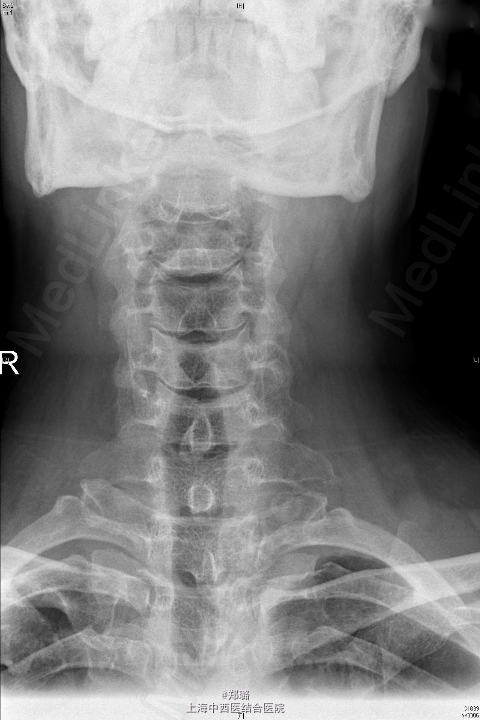

查体:神志清晰,精神尚可,呼吸平稳,营养中等,表情自如,发育正常,自主体位,应答流畅,查体合作。全身皮肤无黄染,无肝掌、蜘蛛痣。全身浅表淋巴结无肿大。脊柱无畸形,生理曲度变直,压颈试验(+),臂丛牵拉试验(+),右肩颈部疼痛,右上臂、前臂桡侧、手部刺痛觉迟钝,双Hoffmann征(-),双侧Babinski征(-);双侧Chaddock征(-),双侧肱二头肌腱膜反射可疑亢进,双侧膝反射正常,四肢肌力尚可。 辅助检查: 外院:CT及MRI(2015-5-19)示:C5/6椎间盘突出,C4/5椎间盘轻度突出 颈椎过伸过屈侧位X线【2015-05-22】 :颈椎动力位未见明显椎体滑脱征象。 颈椎正位(前后位)、侧位X线【2015-05-22】 :颈椎退行性变